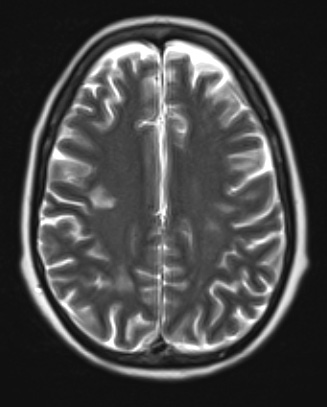

Washington University Experience | NEOPLASMS (HEMATOLYMPHOID) | Lymphoma, Intravascular | 18A2 Lymphoma, intravascular T2 noC - Copy

There are numerous hyperintense white matter lesions visible on this T2-weighted without contrast scan.